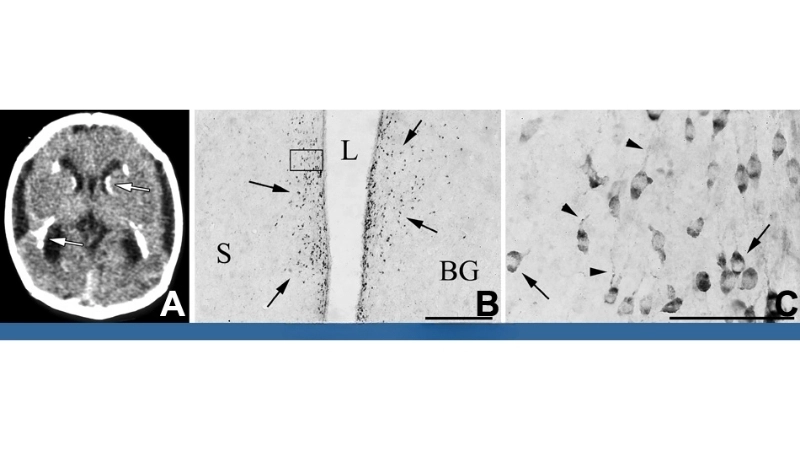

A microscopic view of the LCM virus shows its rodent-transmitted viral particles, highlighting the source and mode of human infection. The virus primarily targets the nervous system, causing inflammation and fever.

LCMV infection can trigger chorioretinitis in patients